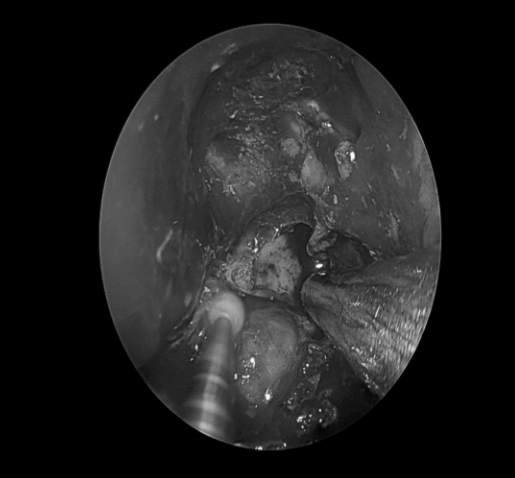

手术经过

拟行鼻内镜下颅底肿瘤切除术(经翼突入路)+双侧鼻息肉切除+双侧鼻窦开窗术+右侧鼓膜切开置管术。